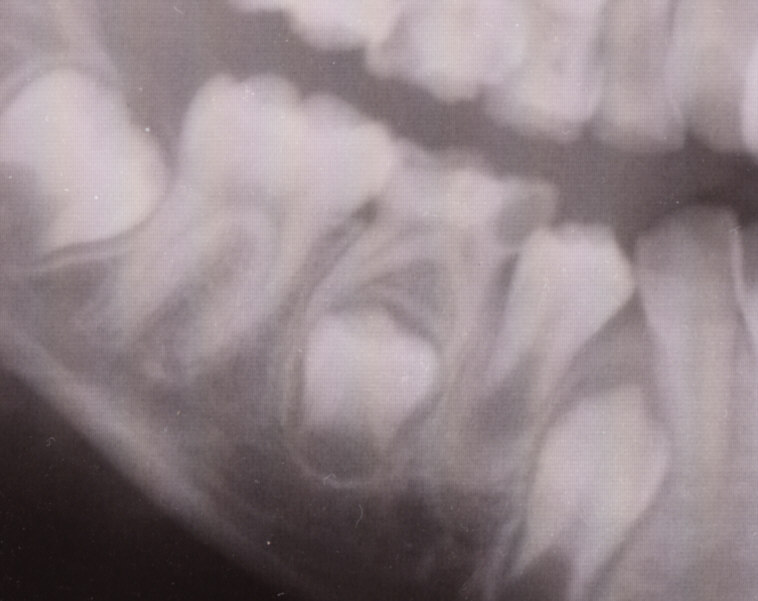

これは乳歯に出来たむし歯のレントゲン写真です。

下の中ほどの歯に黒い穴が開いているのがむし歯です。

その下に永久歯が生えてくる準備を進めているのがお分かりでしょうか。

このむし歯が進んでいけば中の神経も傷み

その下にある永久歯にも影響が出てきます。

細菌が永久歯まで届いてしまえば永久歯の形成が阻害されますし

歯がむし歯で穴が開いたままだと、隣の歯が移動して歯並びが崩れてきます。

乳歯だといって油断せず早めに治療しましょう。